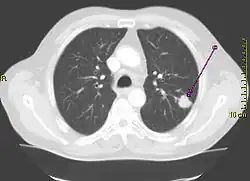

Diagnostik

Eine wichtige Rolle bei der Diagnose eines Bronchialkarzinoms spielen die bildgebenden Verfahren. So sind das Röntgen des Thorax in zwei Ebenen und die Computertomografie (CT) des Thorax die Mittel der Wahl zum Erkennen und Lokalisieren von Bronchialkarzinomen. Die Positronen-Emissions-Tomographie (PET) kann darüber hinaus zum Aufspüren von Fernmetastasen verwendet werden. Die Bronchoskopie wird zur Gewinnung von Gewebeproben für die histologische Beurteilung des Tumors herangezogen. In der Labordiagnostik können die Tumormarker Neuronenspezifische Enolase (NSE) und CYFRA 21-1 zur Diagnosestellung mitverwendet werden, die Ergebnisse sind aber nicht sicher.

Beim kleinzelligen Bronchialkarzinom können zusätzlich die Mediastinoskopie, die Craniale Computertomographie (CCT) oder die Magnetresonanztomografie (MRT) des Kopfes, eine Sonografie („Ultraschall“) des Abdomens zum Ausschluss von Lebermetastasen, CT des Abdomens zum Ausschluss von Leber- und Nebennierenmetastasen sowie eine Knochenszintigraphie zum Ausschluss von Knochenmetastasen hinzukommen.

Trotz modernster Technologie der bildgebenden Verfahren ist die Vorhersagekraft der Computertomografie (CT) alleine zur Beurteilung mediastinaler Lymphknoten zur Stadieneinteilung nicht ausreichend, so dass hier der Mediastinoskopie oder dem EBUS eine große Bedeutung zukommt, falls im CT suspekte Lymphknoten auffallen. Inwieweit die Positronen-Emissions-Tomographie (PET) die Mediastinoskopie ersetzen kann, ist gegenwärtig Ziel verschiedener Untersuchungen. Von besonderer Bedeutung ist die PET, wenn nach einer Induktionstherapie oder Voroperation im Bereich des Mediastinums tumorfreie (negative) mediastinale Lymphknoten über die Indikation zur Operation entscheiden, da die Mediastinoskopie in diesen Fällen eine eingeschränkte Treffsicherheit aufweist. Die Kombination der Aussagen zur Morphologie und Funktion der Lymphknoten mittels Fusion von CT und PET könnte hier weitere Fortschritte ermöglichen.